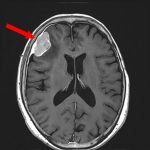

699

'25年11月

50代

左前頭葉腫瘍

頭蓋内腫瘍摘出術

No.’25_101 手術前1

No.’25_101 手術前2

No.’25_101 摘出 前

No.’25_101  摘出 中

No.’25_101 摘出 後